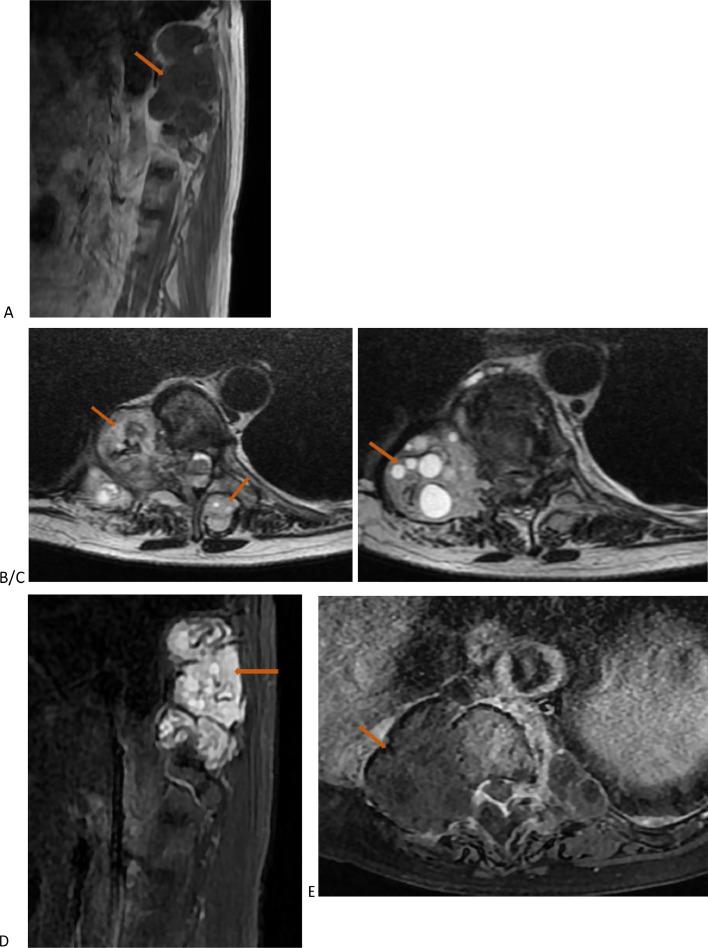

原发性脊椎-髓内及硬膜外包虫病导致髓质受压的罕见病因影像学表现:影像学的作用

Iconographies of rare causes of medullary compression due to primary vertebro-medullary and epidural hydatidosis: Contribution of imaging.

Vertebro-medullary and epidural hydatidosis are a very rare entity, representing 2% of all locations, and is even rarer when it involves a solitary location. It is often asymptomatic. The diagnosis is usually made during complications, particularly medullary compression or extension to the costal cage, which represents a therapeutic emergency. Surgical treatment must be radical to prevent recurrences. We report 2 cases: the first case was a 61-year-old female involved costo-vertebral hydatidosis, and the second was an 18-year-old man with primary sacral epidural location. The objective of our report is to add these 2 atypical locations of hydatid cysts to the existing literature and to present their radiological images to aid radiologists in diagnosis.

摘要

脊椎-髓内和硬膜外包虫病是一种非常罕见的疾病,占所有发病部位的2%,当它累及单一部位时更为罕见。它通常无症状。诊断通常在出现并发症时做出,特别是髓内压迫或向胸廓扩展,这是一种治疗急症。手术治疗必须彻底以防止复发。我们报告2例:第一例是一名61岁女性,患有肋-椎包虫病,第二例是一名18岁男性,原发性骶部硬膜外发病。我们报告的目的是将这2个包虫囊肿的非典型发病部位补充到现有文献中,并展示其放射影像以帮助放射科医生进行诊断。